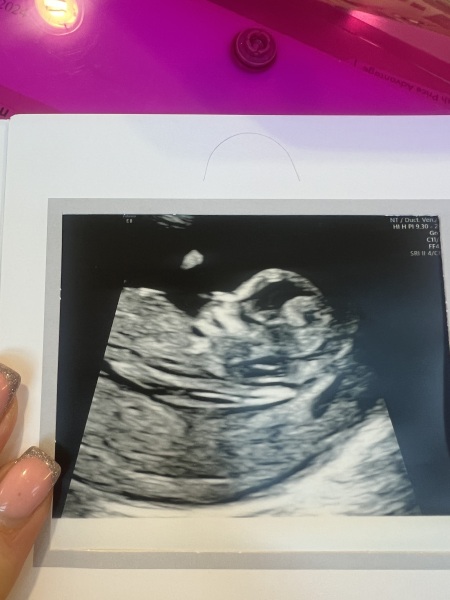

thought I’d update you all, I had another little bit of spotting on 21st December (my bday) lol, of course - ended up paying for a private scan to check everything was ok but it was the best money I ever spent… pic below, she said everything is absolutely perfect and nothing at all to worry about she said if the spotting comes back just to ignore it if it’s not too heavy. She can’t see a reason for it at all! So maybe just hormonal.

Hi ladies! Yes went perfectly no issues. The baby was moving soo much it was making me laugh. Took her ages to get the measurements she needed. Very grateful it’s all good. How did yours go?

ps - my scan pic is so clear I can’t believe I can see baby’s face?! Lol

@JDecember21 wow!!

Your scan is amazing, always makes me laugh how their little noses look 🤣

Glad your scans went so well @JDecember21 and @sellingupslow , lovely scan images!